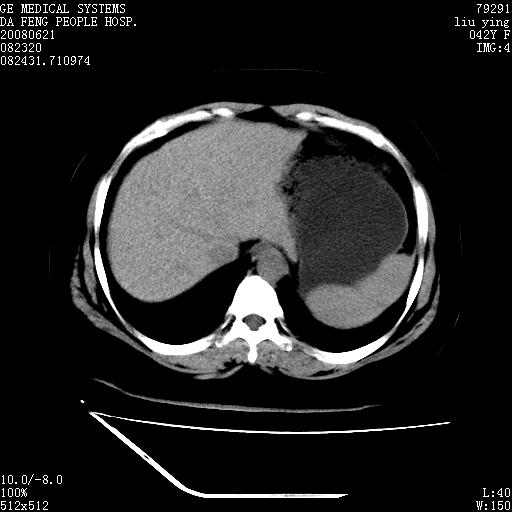

标题: CT14225:女性46岁。当地B超示肝内占位,来我院作CT检查。请 [打印本页]

标题: CT14225:女性46岁。当地B超示肝内占位,来我院作CT检查。请

速升速降,支持肝癌.脾体积增大,形态欠规整,请询问病史是否做过脾动脉栓塞.

速升速降,支持肝癌可能。

快进快出,符合肝癌表现-----------

肝内结节强化特点符合原发性肝癌表现,脾脏改变考虑为增大及先天发育所致。

动脉期病原灶明显强化高于肝密度且中央有无强化区,静脉期强化程度下降明显,延迟低于肝密度,考虑肝腺瘤可能性大,

肝内结节强化特点:快进快出符合原发性肝癌表现

此患者虽然符合快进的特点,却不符合快出的特点,因为门脉期几乎是等密度,不符合肝癌的增强表现,所以我考虑肝局灶性结节增生可能性大